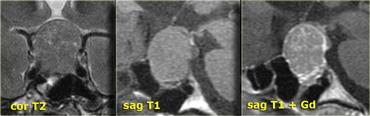

Các chuỗi xung T1W, T2W và T1W sau tiêm gadolinium này minh họa một nang khe Rathke khác nằm trong tuyến yên.

Khác với mô tuyến yên bình thường và cuống tuyến yên, nang không ngấm thuốc sau khi tiêm thuốc tương phản từ tĩnh mạch.

Mô tuyến yên bình thường bị chèn ép và đẩy lệch sang bên trái. Điều quan trọng là cần nhận biết điều này vì có thể nhầm lẫn với thành phần ngấm thuốc của khối dạng nang.

Nhìn chung, tất cả các khối ngoài trục, tức là các khối nằm ngoài não như tuyến yên và cuống tuyến yên, đều sẽ ngấm thuốc vì chúng không có hàng rào máu-não.

Nếu gặp một khối ngoài trục không ngấm thuốc, có ba khả năng:

- Dòng chảy động mạch nhanh (ví dụ: mạch máu lớn).

- Không có mô tế bào (ví dụ: nang).

- Không có nguồn cung cấp máu (ví dụ: khối bị nhồi máu).